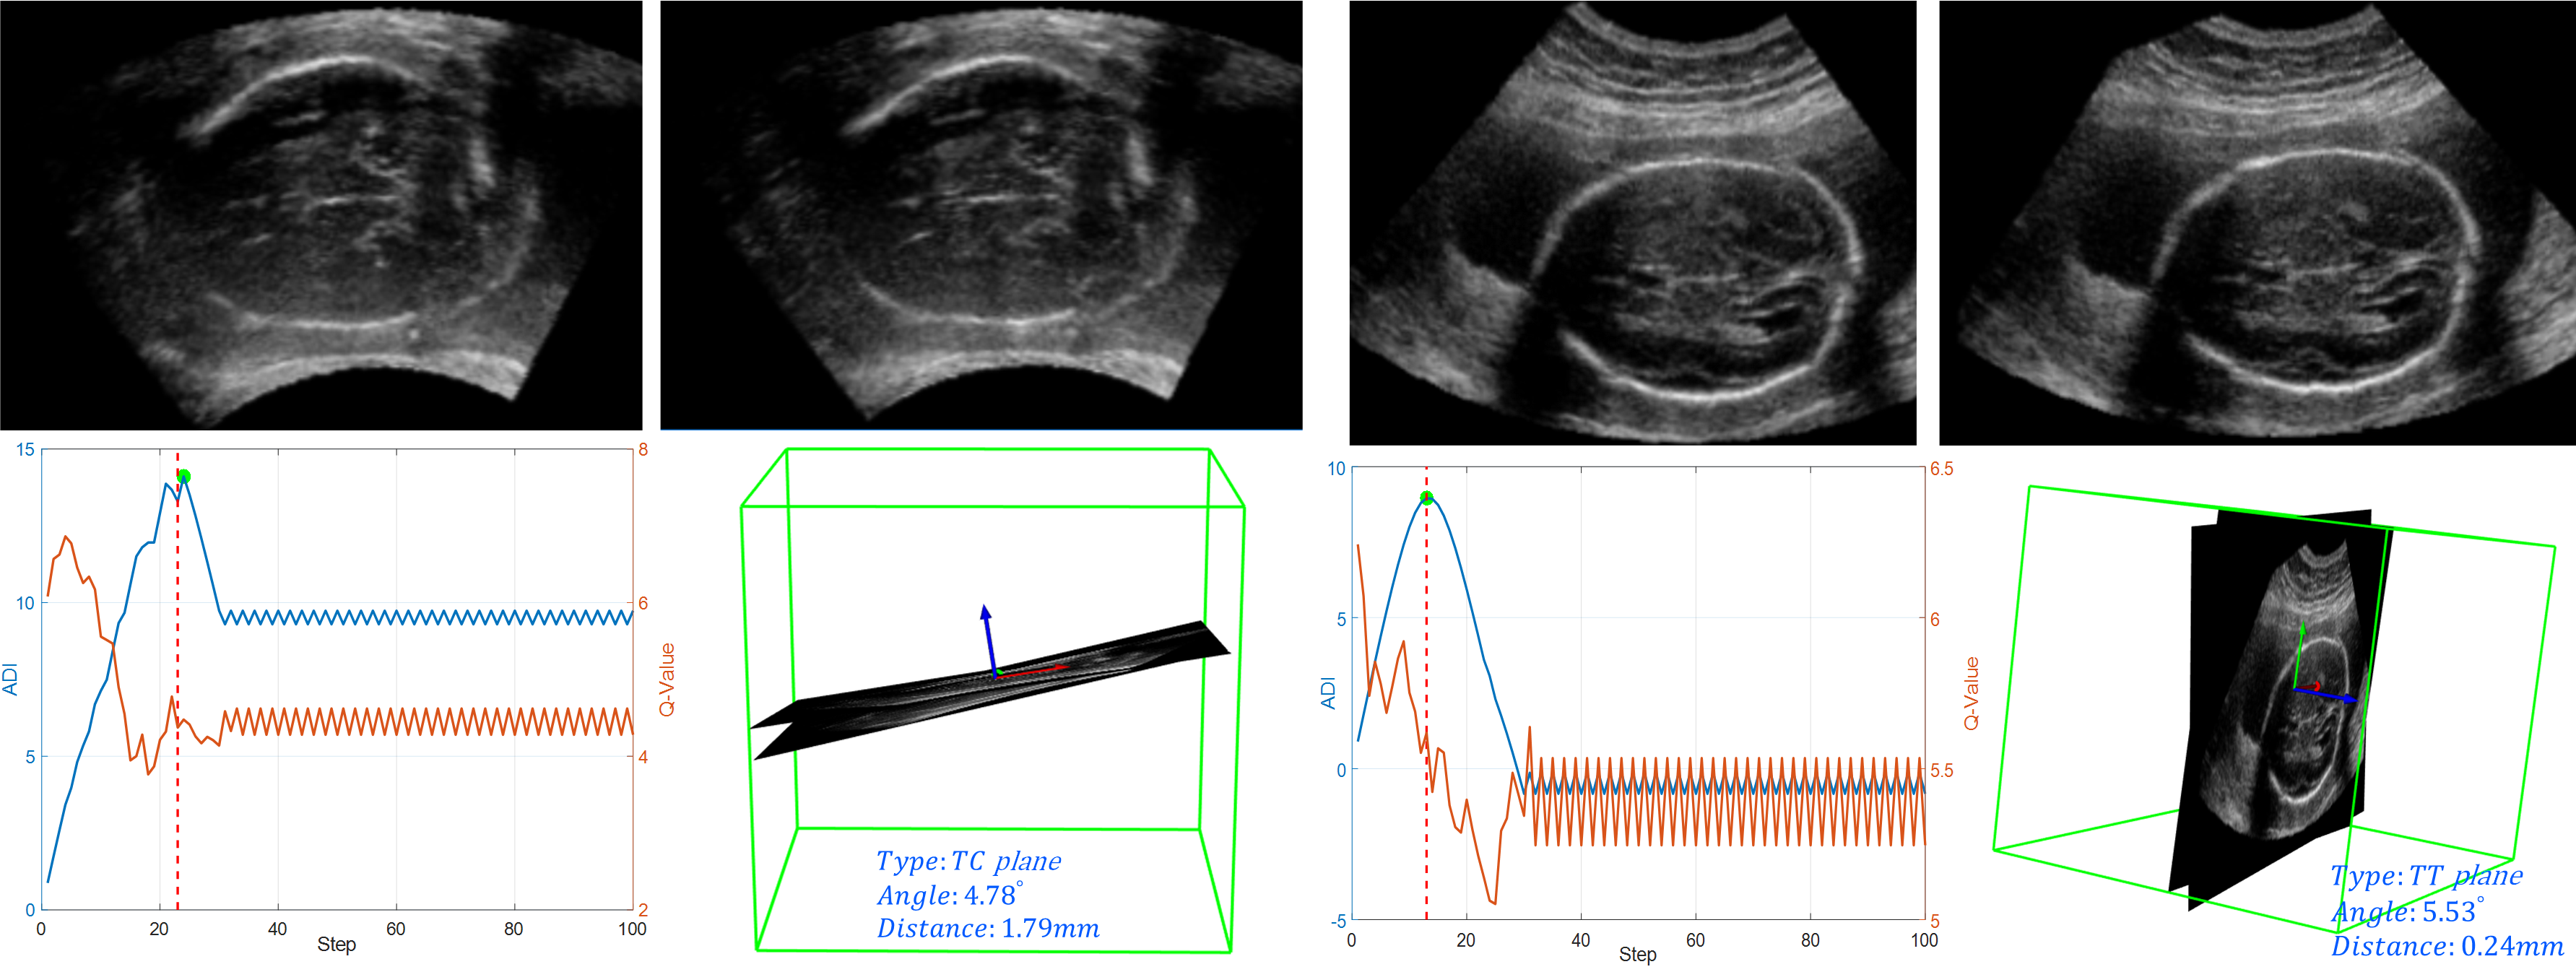

Figure 5: TC (left) and TT (right) results. Top row: ground truth (left) and predicted (right) plane. Bottom row: left, active termination step (dotted red line) compared to optimal step in green dot, 3D visualization of ground truth and predicted plane (right).

In Fig. 5, we visualize two testing results of DDQN-AT (LSTM) for TC and TT plane localization. Compared from image content and spatial relationship, for both tasks, our method accurately captures the plane, which is very close to the ground truth. Our active termination strategy also presents the ability to learn from the Q-value sequence and hits the optimal termination step (green dot) for large angle and distance improvement (ADI).